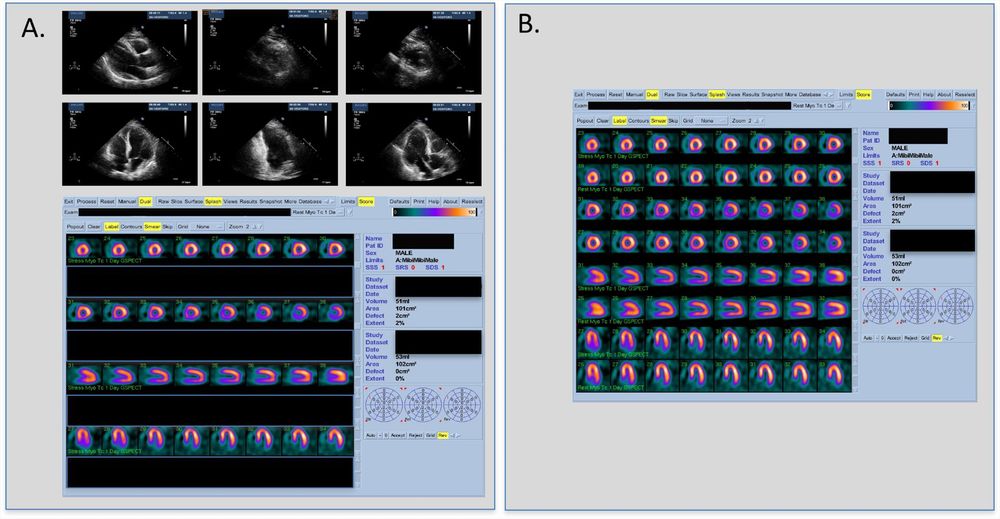

latest research by Szmigielski et al explores🌟ECHO-MPS, a dual modality strategy of #CVImaging to identify myocardial ischemia🌟Dive deeper in #IJCVI 🌐 doi.org/10.1007/s105...

ECHO-MPS, a dual modality strategy of cardiac imaging to identify myocardial ischemia

The International Journal of Cardiovascular Imaging - We aimed to evaluate an approach with resting echocardiography (TTE) and stress myocardial perfusion scintigraphy (MPS) compared to standard...

doi.org